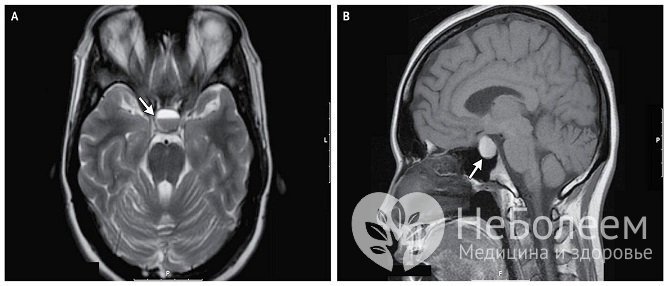

Иногда требуется дополнительное проведение пневмоцистернографии (позволяет выявить смещение хиазмальных цистерн и признаки пустого турецкого седла), компьютерной и магниторезонансной томографии. В 25–35% аденомы гипофиза имеют столь малый размер, что их визуализация затруднительна даже при использовании современных средств диагностики.

Аденома гипофиза диагностирована при проведении МРТ турецкого седлаНемаловажное значение для постановки диагноза имеет лабораторное определение концентрации гормонов гипофиза в крови пациента радиоиммунологическим методом. В зависимости от имеющихся клинических проявлений может возникнуть необходимость в определении концентрации гормонов, вырабатываемых периферическими железами внутренней секреции.